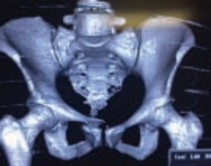

Рис. 5. Рентгенограмма таза и КТ тазового кольца с 3Д реконструкцией пациента до операции

Клиническое наблюдение 2: Пациент М., 54 года, травма получена при падении, во время катании на лыжах, доставлен в день травмы в стационар бригадой МЧС в противошоковом костюме. Диагноз при поступлении: Политравма. ЗЧМТ. Сотрясение головного мозга. Изолированный нестабильный перелом костей таза В3 по классификации А.О., состояние пациента по шкале ISS - 20 баллов. Учитывая характер травмы, отсутствие других повреждений, решено оперировать пациента на следующие сутки после травмы, а предоперационную подготовку продолжить в ОРИТ. При поступлении гемоглобин 100 г/л, гематокрит 27%. На следующий день пациенту была выполнена открытая стабилизация переднего полукольца пластиной А.О., стабилизация заднего полукольца винтами А.О. Ранний послеоперационный период протекал без особенностей, проводилась симптоматическая, антибактериальная, инфузионная, антикоагулянтная терапия. С третьего дня от момента операции начата ЛФК. Пациент выписан в удовлетворительном состоянии из стационара на 17 сутки от момента травмы. Через год рентгенологический и функциональный результат хороший.